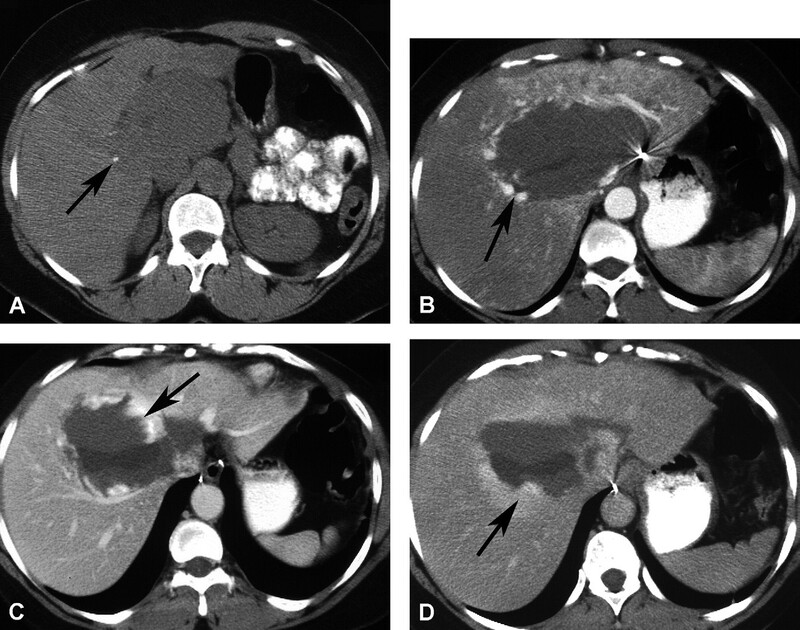

Hemangioma là u gan lành tính thường gặp nhất. Hemangioma thường gặp ở phụ nữ trẻ và 15-20% nhiều ổ. Mô học cho thấy một loạt các hồ máu và kênh mạch, các tổn thương lớn hơn tạo ra các vùng huyết khối và xơ. Siêu âm thấy một khối tăng âm, đồng nhất, giới hạn rõ, tăng âm phía sau yếu (Hình 1). Các tổn thương lớn hơn (>6cm) có thể không đồng nhất và giảm âm do huyết khối, hoại tử và thoái hóa nang. Các dấu hiệu CT cản quang gồm tăng quang dạng nốt ngoại vi ở thì động mạch với lấp đầy hướng tâm dần trong tổn thương ở thì tĩnh mạch cửa và thì muộn (hình 2). Vôi tĩnh mạch (phlebolith) có thể thấy trong tổn thương ở 15-20% trường hợp (Hình 2). MRI cho thấy tăng tín hiệu trung bình trên T2W, thường ít hơn so với nang đơn thuần, tín hiệu thấp trên T1W. MRI sau tiêm thuốc cho thấy bắt thuốc dạng nốt gián đoạn phía ngoại vi ở thì động mạch, đó là đặc điểm điển hình của hemangioma (Hình 3). MRI thì tĩnh mạch và thì muộn có thể thấy các nốt bắt thuốc lớn dần và hợp lưu với lấp dầy trung tâm ở các mức độ khác nhau tương tự như CT.

Hình 2. Bệnh nhân nữ 42 tuổi, hemnagioma. CT không cản quang (A) thấy đốm đóng vôi (mũi tên) ở ngoại vi khối giảm đậm độ gợi ý vôi tĩnh mạch. Có tăng quang dạng nốt ngoại vi (mũi tên ) ở thì động mạch (B), lấp vào trung tâm (mũi tên) ở thì tĩnh mạch cửa (C). Thì muộn (D) thấy lấp vào một phần tổn thương (mũi tên) do huyết khối.